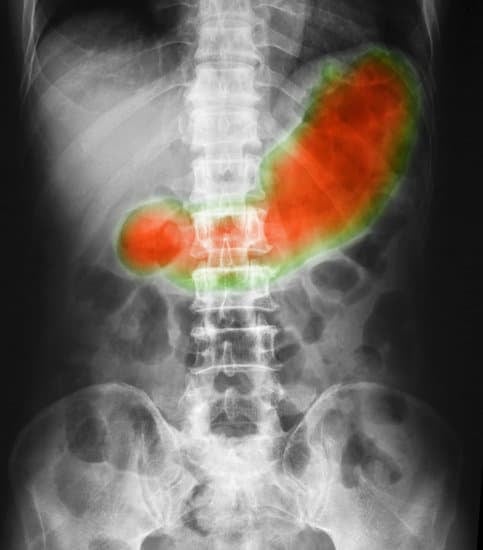

영상 검사

위장 X-ray(조영술) 또는 CT를 통해 위의 위치와 모양 확인.

위가 골반 부위까지 내려가 있으면 위하수증으로 진단.